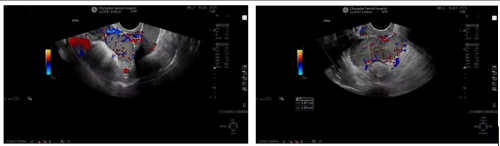

超声显示盆腔内多发肿物,考虑种植脾

11月20日,张芸在长沙市中心医院健康管理中心接受常规超声检查时,发现了盆腔内多发肿物,且性质较为复杂,无法明确其具体性质,随后,张芸在妇产科三区住院接受进一步诊治。完善盆腔MRI及彩超检查等一系列检查后,结果仍未能准确认定盆底肿物的起源及性质。鉴于张芸病情的特殊性,妇产科三区主任魏馨带领团队深入探讨、广泛查阅相关文献资料,并组织院内多学科会诊,最后诊断盆腔肿物为脾脏组织,免除了张芸遭受手术的痛苦。